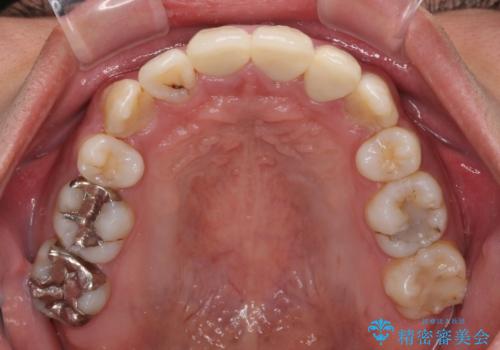

前歯は根管治療が必要な歯を事前に根管治療を行い、矯正治療後にオールセラミッククラウンにて補綴治療を行うこととしました。

前歯の歯列が整ったことで、歯磨きが大変やりやすくなり、患者様には大変満足していただけました。